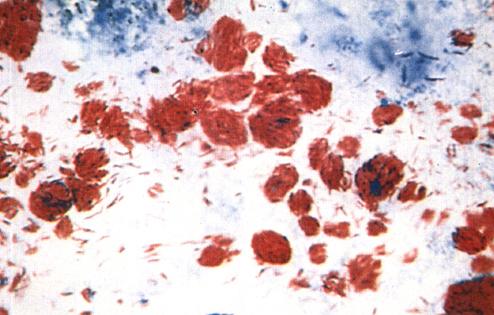

一、麻风杆菌的一般特征(图1-1a)

图1-1(a)

ML经萋-尼氏(Ziehl-Neelsen)抗酸染色法(简称Z-N法)染色在光学显微镜下可看到菌体被染成红色,呈直或略弯曲的杆菌,长1~8微米,宽0.3~0.4微米。ML无鞭毛、无芽孢,至于有无荚膜的问题,至今仍有争论

ML对抗酸染色、革兰氏染色均呈阳性。前者称为ML的抗酸性,这不是指ML有抵抗酸性物质的能力,而是指在用Z-N法染色时,ML能被石碳酸复红染成红色,着色后在规定条件下不能被酸性溶液(或酸醇溶液)脱色的现象。这种抗酸性可经新鲜、纯净的吡啶提取(2小时)而丧失,也可经过碘酸处理而恢复。Convit认为这是ML独有的,是鉴定ML的重要标准之一。我国吴勤学氏支持Convit的观点。

形态上的多形性是ML的另一特点。麻风病人组织涂片经Z-N法染色后在光学显微镜下能看到杆状的着色均匀的菌,也可看到短杆状、断裂状、串珠状及颗粒状等形态的菌。细菌形态与病人治疗情况有密切的关系。许多细菌学家认为,这种多形性是ML生命周期(1ife cycle)的一部分或是ML的芽孢型(spore form),Rees等人以光学显微镜和电子显微镜进行对比观察后认为,那些不规则染色的菌是无活力的,是由于菌死后细胞内含物部分损失所致(图1-1b)。